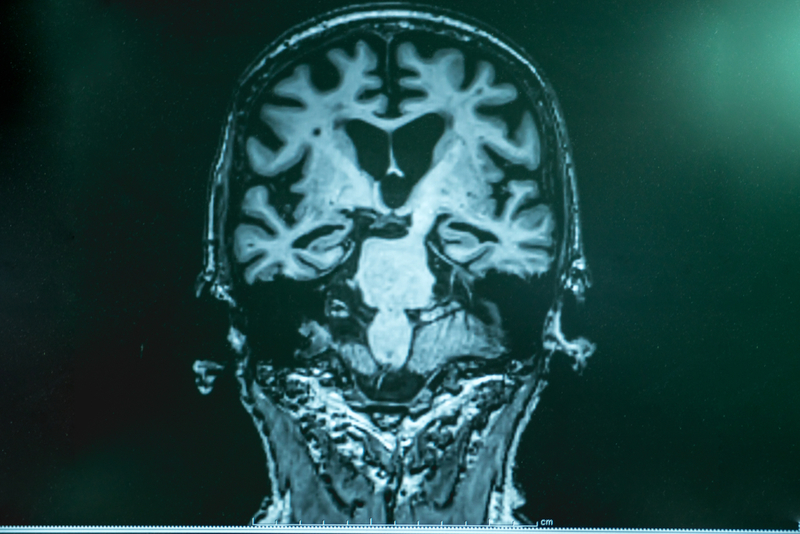

In patients with Alzheimer’s disease, the hippocampus and entorhinal cortex are frequently affected at an early stage, and these individuals often lose their way and cannot recognise their environment. Knowledge about the brain’s positioning system may, therefore, help with understanding the mechanism underpinning the significant spatial memory loss that affects people with this disease, Professor Moser will propose.